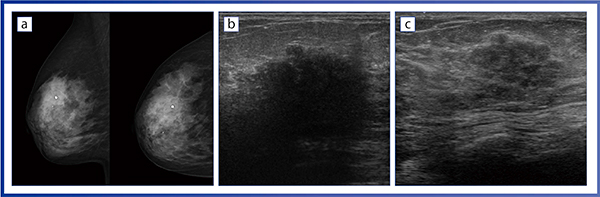

症例1は,29歳の方で,超音波検診にて異常を指摘された。マンモグラフィでは,右MIOにspiculated massが描出されており,カテゴリー5と診断されるような悪性が強く疑われる症例である(図1 a)。エコーでは細かい分葉型腫瘤になっており,内部エコーも硬癌ほど低エコーではない(図1 b)。後方エコーは減弱している箇所と増強している箇所があり,これは多様な内部エコーの反射の影響を受けていると推察され,縦方向からの観察でも同様であることから,硬癌ではないと考えた。動画像でも,構築の乱れを観察でき,これがマンモグラフィ画像のスピキュラとして描出されていたと見られ,硬化性腺症が疑われた。

エラストグラフィでは,あまり硬さが見られず,SMI(Superb Micro-vascular Imaging)でも血流は少なく描出されている。なお,Aplio iシリーズでは,病変部をスイープスキャンしてSMIのデータから3D画像を作成することで,より微細な血管の構築を立体的に観察することが可能となった(図1 c)。さらに,iBeam Slicingによって,薄いスライス厚でSMIを撮像できることから,腫瘤の血管構築の観察などに役立つと期待している。

本症例の造影MRマンモグラフィでは,腫瘤の部分に強い増強効果があり,硬化性腺症の中に非浸潤性乳管癌(以下,DCIS)の可能性が示唆され,切除術が施行された(図1 d)。病理像は非常に多彩で,乳管内病変やコロイド,病的な間質が存在しており,硬化性の変化によってスピキュラを呈していたと推察される。さらに,乳管内病変に乳頭腫があり,ごく一部にDCISが混在していた(図1 e)。術前の超音波検査では検出できなかった6mmの乳腺管状癌も見つかっており,広範囲の良性病変の中に悪性腫瘍が見られた症例であった。この病理像を踏まえて,Bモード画像を見直すと,硬化の度合いが異なる乳管内病変と,拡張した乳管が描出されていることがわかる(図1 f)。また,内部エコーが硬癌のような低エコーではないのは,乳管内乳頭腫と間質,さらには粘液様のものが混在して高エコーになっていると思われた。24MHzのPLI-2004BXによるBモード画像は,このような複雑な病態を明瞭に描出できている。

図1 症例1

a:マンモグラフィ画像 b:Bモード画像 c:Smart 3DによるSMI画像

d:病理像とBモード画像の対比 e:病理像 f:eのBモード画像